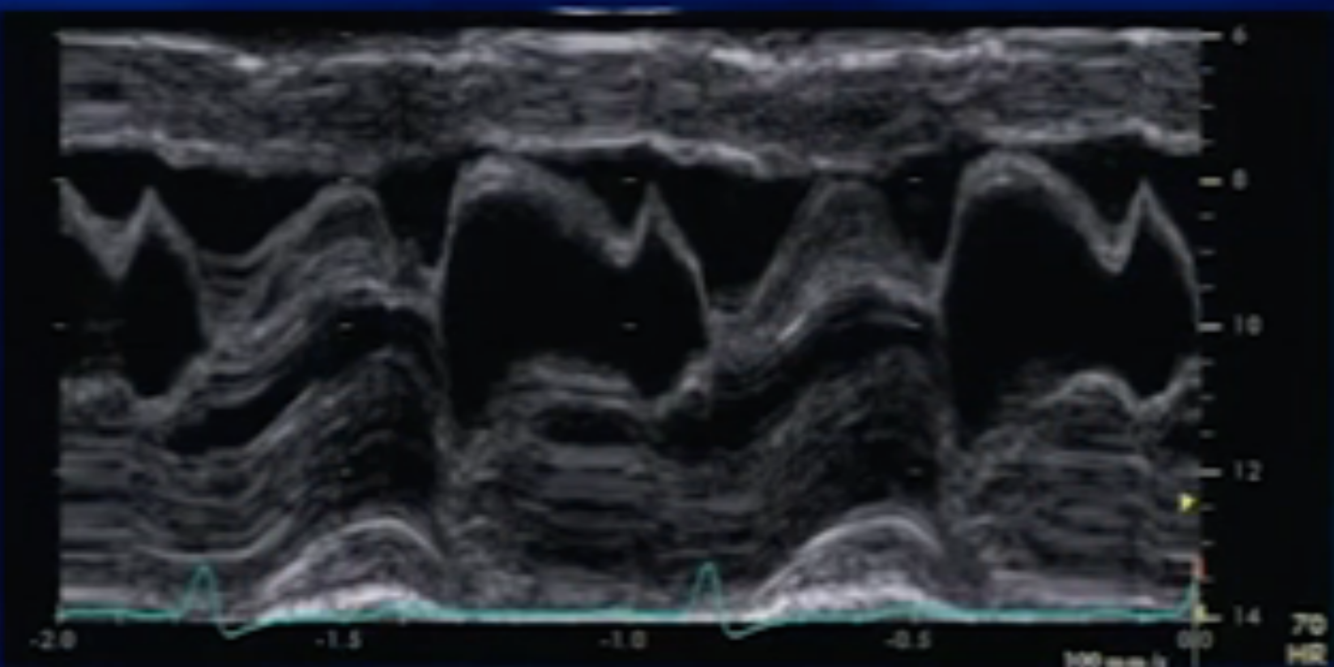

Diagnosis

MVP ( >3mm systolic bowing BELOW the C-D line)